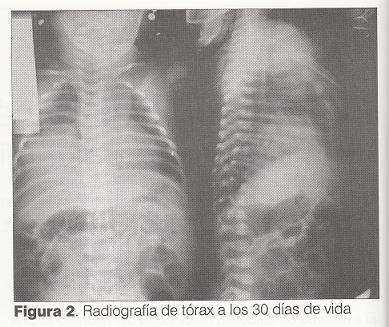

Durante el primer mes de vida se realizaron controles médicos sucesivos y radiografía de tórax (figura 2).

Clínicamente estuvo asintomática, con buen progreso ponderal (1.070 gramos de incremento a los 37 días de vida).

A los 45 días de vida se realizó radioscopía y ecografía torácica que evidenció deformidad sectorial del hemidiafragma derecho en su sector medio; el sector anterior y posterior se movilizaban simétricamente con el contralateral, el sector medio se movilizaba en menor grado. El diagnóstico imagenológico fue de debilidad sectorial de hemidiafragma derecho.